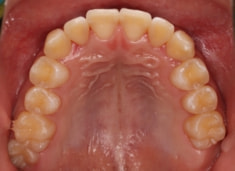

治療開始時

FX(フェイシャルアキシス)は85度なので東洋人の平均値に近く、下顎が前方に過剰成長するリスクは強くはありません。

しかしやはり上顎は劣成長で、下顎が優位な状態ではあります。

上下顎のギャップはありますが、顔面自体の幅径は良好な値を示していますので、スペース不足は拡大することによって解決できポテンシャルはあると考えられます。

左右の非対称もさほど強くありません。